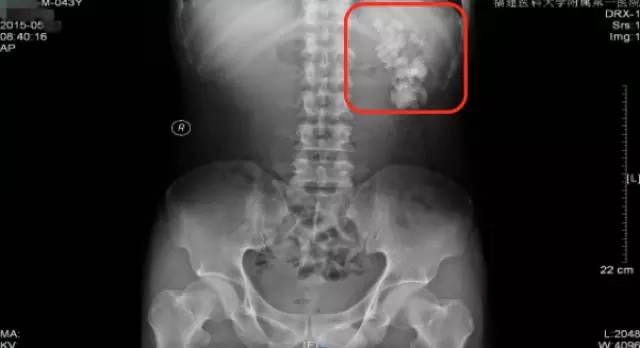

第二次来福建医科大学附属第一医院复查KUB检查结果

通过与4个月前的片子对比,我们可以看到虽然经过了两次手术,但是左肾区仍然遗留了大量而且分散的结石,甚至输尿管上段都有结石卡住(白色箭头所指结石),所以其症状仍然反复。

从他复查的这个KUB上,我们可以看到,左肾仍然有很多结石,而且还有结石掉到左侧输尿管上段引起了梗阻。这种结石如果不取干净,他肾脏里的结石就会时不时掉下来一颗两颗的,堵住输尿管,最终一定会把这个肾脏搞坏掉,我果断通知患者立马住院。